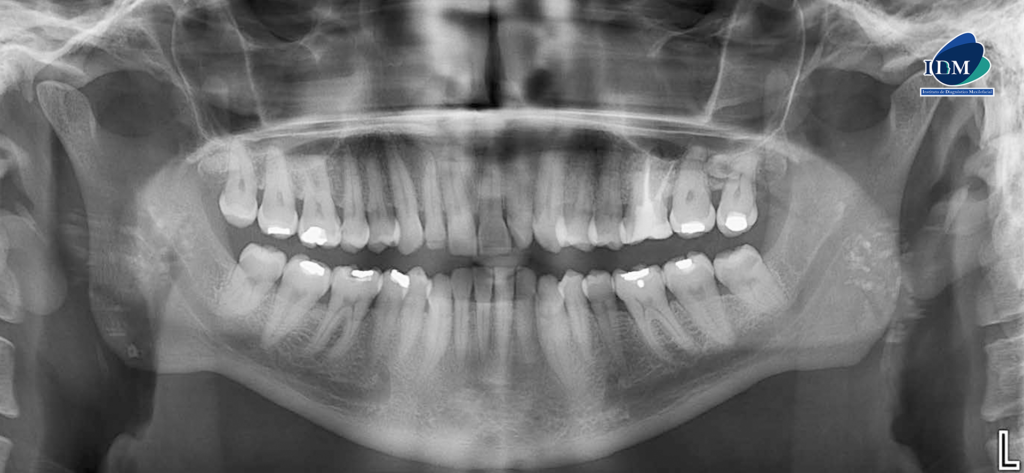

Radiografia Panorámica

En la radiografía panorámica se observan imágenes radiopacas proyectadas en las ramas ascendentes y región de vía aérea adyacente, compatibles con tonsilolitos. A nivel del segundo cuadrante se observa una pieza supernumeraria proyectada sobre las raíces de las

piezas 27 y 28.